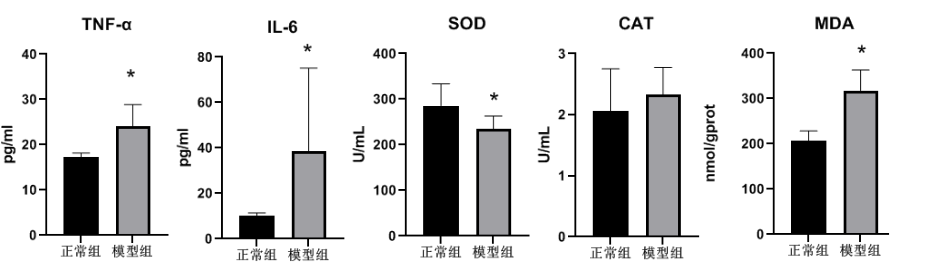

勋博生物乙醇通过直接损伤胃黏膜屏障诱导急性溃疡。其机制包括:①破坏胃黏膜黏液-碳酸氢盐屏障,增加H⁺反向扩散;②抑制环氧合酶活性,降低前列腺素E2(PGE2)合成;③激活中性粒细胞浸润,升高髓过氧化物酶(MPO)及炎症因子(TNF-α、IL-6)。研究表明,乙醇浓度与损伤程度呈正相关,85%-100%乙醇可造成典型出血性溃疡。

- 观察指标:除了临床症状外,还可以结合组织学观察、生化指标检测等手段对胃溃疡的形成和愈合过程进行深入研究。组织学观察可以评估胃溃疡的面积、深度以及胃黏膜的炎症程度等指标;生化指标检测可以评估胃黏膜的屏障功能、氧化应激水平等指标。

损伤评估:宏观观察胃黏膜出血、糜烂灶,计算溃疡指数(UI):溃疡长度>1 mm计1分,宽度>1 mm追加1分。组织学切片(HE染色)评估黏膜上皮脱落、炎性浸润及出血深度。

- 观察指标:除了溃疡指数外,还可以结合组织学观察、生化指标检测等手段对胃溃疡的形成和愈合过程进行深入研究。